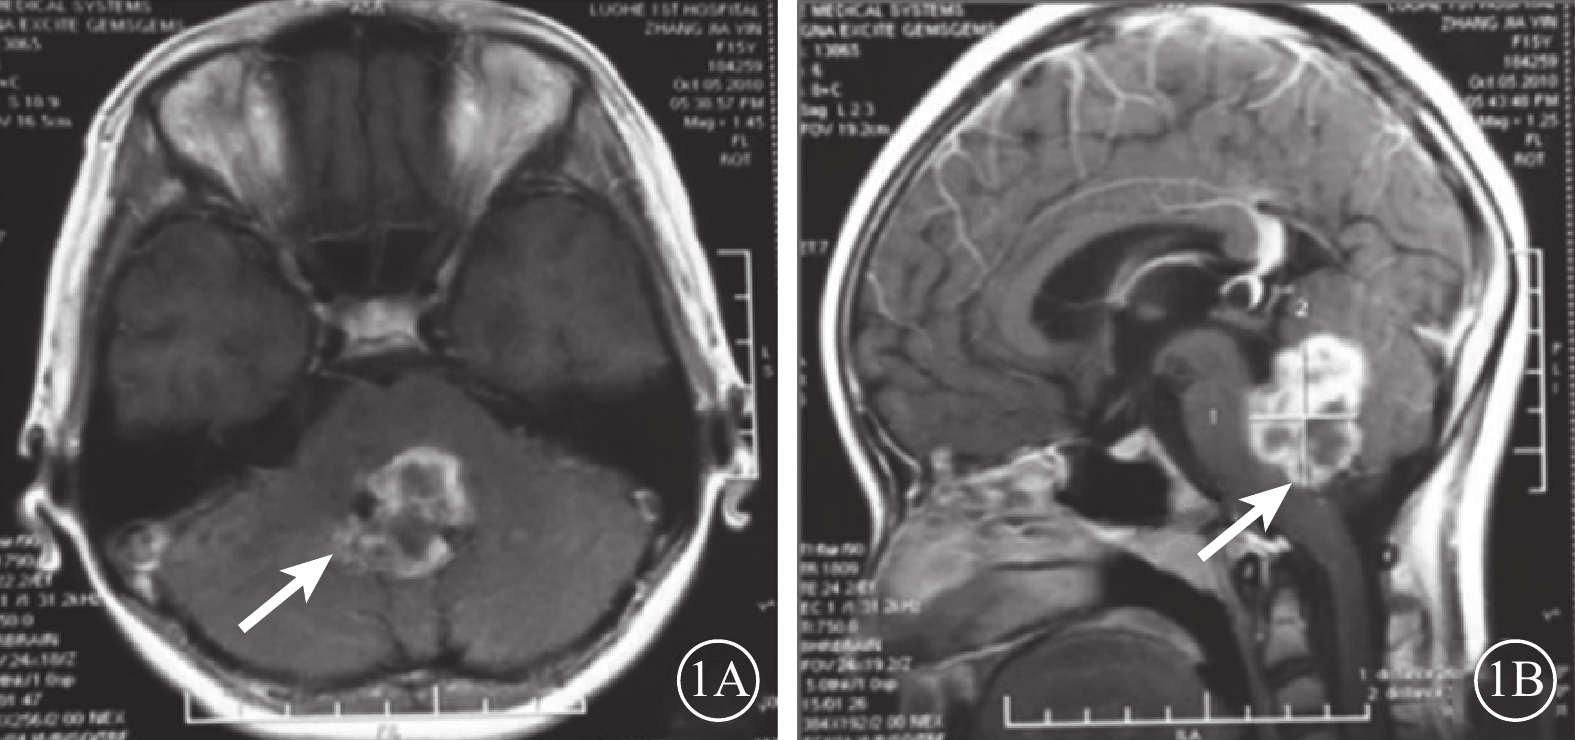

患者女,18歲。2010年9月因頭枕部外傷致意識喪失入院。醒后發現左眼內斜、眼球運動障礙、視力下降伴口角右偏。眼眶CT檢查未見異常;頭顱MRI檢查顯示小腦蚓部出血致雙側小腦半球、第四腦室及背側腦橋受壓變形(圖1)。傷后10 d行顱內血腫清除手術。手術后上述癥狀無改善且逐漸出現左眼瞼閉合不全、視力逐漸下降。為求進一步診治于2015年12月到我科就診。否認既往眼病及全身病史。眼部檢查:右眼視力1.0;左眼視力0.1,不能矯正。雙眼瞳孔等大,對光反射靈敏;左眼相對性瞳孔傳入性障礙(+)。雙眼視盤邊界清楚,顏色淡,以左眼為著;黃斑中心凹反光清晰。雙眼眼壓正常。視野檢查,右眼生理盲點擴大,鼻下象限視野部分缺損,視敏度下降;左眼顳側及鼻上象限視野不規則缺損。光相干斷層掃描檢查,雙眼視盤周圍視網膜神經纖維層變薄。眼位檢查,右眼注視時左眼內斜約30°;左眼注視不良。眼球運動檢查,右眼外展正常伴輕度水平眼球震顫,內收受限,鼻側角膜緣僅到達上、下淚小點連線;左眼外展受限,顳側角膜緣剛過中線,內收正常(圖2),單眼和雙眼運動相同;輻輳反射正常。神經系統檢查,左側額紋消失,瞼裂閉合不全,鼻唇溝變淺,舌前2/3味覺減退;口角向右偏斜,鼓腮時左側漏氣。診斷:(1)麻痹性內斜視;(2)非典型性八個半綜合征;(3)外傷性視交叉病變;(4)雙眼視神經萎縮。行左眼上、下直肌1/2轉位聯合內直肌后退手術。手術后眼位正,隨訪半年眼位穩定。

頭顱MRI像。1A. 平掃軸位T1像;1B. 增強掃描矢狀位T1像。小腦蚓部出血導致第四腦室及背側腦橋受壓變形(白箭)

頭顱MRI像。1A. 平掃軸位T1像;1B. 增強掃描矢狀位T1像。小腦蚓部出血導致第四腦室及背側腦橋受壓變形(白箭)

本例患者頭枕部外傷導致顱內小腦蚓部出血,第四腦室和背側腦橋受壓,損傷左側腦橋側視中樞和面神經膝,繼而患側眼球不能外展但內收正常,健側眼球內收受限但外展正常,同時合并患側周圍性面癱。由于缺少患側內側縱束損傷,故為非典型性八個半綜合征。患者損傷部位定位在左側腦橋尾部被蓋區,但病變僅累及患側側視中樞和面神經膝,未波及患側內側縱束。但若患側內側縱束未遭受任何侵害,則患者健眼外展時不應出現水平眼震。而本例患者健眼外展時伴有眼震,其原因可能是患側內側縱束輕微損害導致對患眼內直肌興奮性神經纖維和健眼內直肌抑制性神經纖維的支配減弱,使得健眼內直肌的興奮性增高,但未表現出患眼內收運動障礙。另外,患者雙眼視野損傷及左側為著的雙側視神經萎縮應為視交叉左后下方受損所致。

患者女,18歲。2010年9月因頭枕部外傷致意識喪失入院。醒后發現左眼內斜、眼球運動障礙、視力下降伴口角右偏。眼眶CT檢查未見異常;頭顱MRI檢查顯示小腦蚓部出血致雙側小腦半球、第四腦室及背側腦橋受壓變形(圖1)。傷后10 d行顱內血腫清除手術。手術后上述癥狀無改善且逐漸出現左眼瞼閉合不全、視力逐漸下降。為求進一步診治于2015年12月到我科就診。否認既往眼病及全身病史。眼部檢查:右眼視力1.0;左眼視力0.1,不能矯正。雙眼瞳孔等大,對光反射靈敏;左眼相對性瞳孔傳入性障礙(+)。雙眼視盤邊界清楚,顏色淡,以左眼為著;黃斑中心凹反光清晰。雙眼眼壓正常。視野檢查,右眼生理盲點擴大,鼻下象限視野部分缺損,視敏度下降;左眼顳側及鼻上象限視野不規則缺損。光相干斷層掃描檢查,雙眼視盤周圍視網膜神經纖維層變薄。眼位檢查,右眼注視時左眼內斜約30°;左眼注視不良。眼球運動檢查,右眼外展正常伴輕度水平眼球震顫,內收受限,鼻側角膜緣僅到達上、下淚小點連線;左眼外展受限,顳側角膜緣剛過中線,內收正常(圖2),單眼和雙眼運動相同;輻輳反射正常。神經系統檢查,左側額紋消失,瞼裂閉合不全,鼻唇溝變淺,舌前2/3味覺減退;口角向右偏斜,鼓腮時左側漏氣。診斷:(1)麻痹性內斜視;(2)非典型性八個半綜合征;(3)外傷性視交叉病變;(4)雙眼視神經萎縮。行左眼上、下直肌1/2轉位聯合內直肌后退手術。手術后眼位正,隨訪半年眼位穩定。

頭顱MRI像。1A. 平掃軸位T1像;1B. 增強掃描矢狀位T1像。小腦蚓部出血導致第四腦室及背側腦橋受壓變形(白箭)

頭顱MRI像。1A. 平掃軸位T1像;1B. 增強掃描矢狀位T1像。小腦蚓部出血導致第四腦室及背側腦橋受壓變形(白箭)

本例患者頭枕部外傷導致顱內小腦蚓部出血,第四腦室和背側腦橋受壓,損傷左側腦橋側視中樞和面神經膝,繼而患側眼球不能外展但內收正常,健側眼球內收受限但外展正常,同時合并患側周圍性面癱。由于缺少患側內側縱束損傷,故為非典型性八個半綜合征。患者損傷部位定位在左側腦橋尾部被蓋區,但病變僅累及患側側視中樞和面神經膝,未波及患側內側縱束。但若患側內側縱束未遭受任何侵害,則患者健眼外展時不應出現水平眼震。而本例患者健眼外展時伴有眼震,其原因可能是患側內側縱束輕微損害導致對患眼內直肌興奮性神經纖維和健眼內直肌抑制性神經纖維的支配減弱,使得健眼內直肌的興奮性增高,但未表現出患眼內收運動障礙。另外,患者雙眼視野損傷及左側為著的雙側視神經萎縮應為視交叉左后下方受損所致。